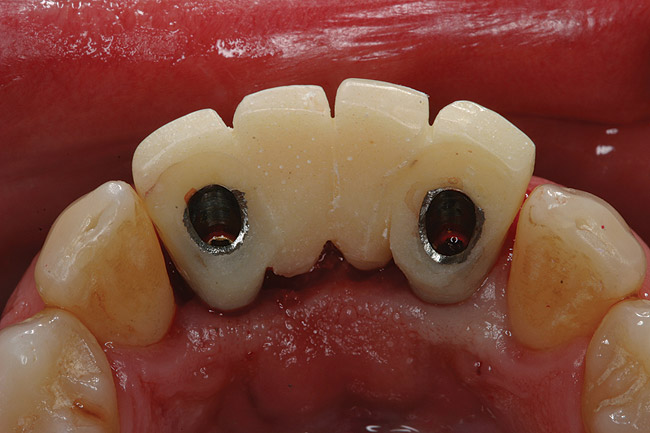

Figure 4  Tapered implants with conical transgingival abutments and temporary cylinders in place.

Figure 4

Figure 5  Surgical guide acts as provisional positioning appliance; temporary cylinders are placed, and acrylic resin is added to connect to processed provisional.

Figure 5

Figure 6a  Screw-retained provisional restoration with ovate pontics (with particulate allograft material in sockets). Inside view.

Figure 6a

Figure 6b  Screw-retained provisional restoration with ovate pontics (with particulate allograft material in sockets). Front view.

Figure 6b